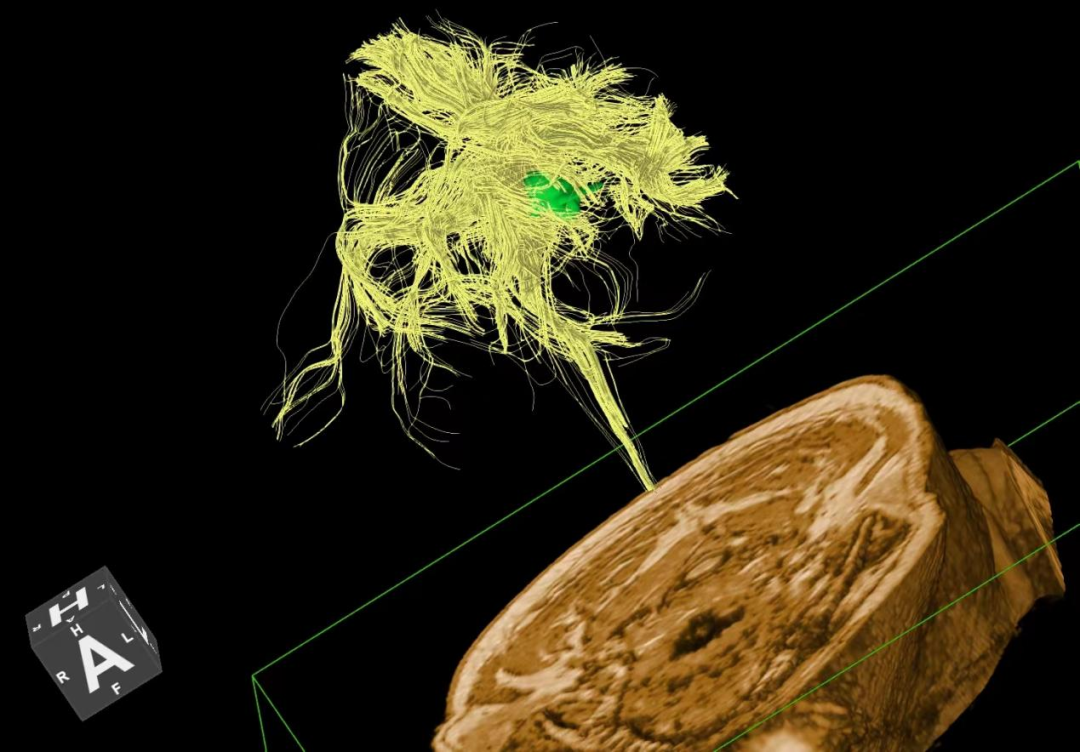

(颅脑DTI成像)

此外,联影智能光梭uMR790 3.0T 磁共振具有丰富的扫描检查模式,能够完成包括神经系统、胸部、腹部、盆腔、心血管、骨骼关节、软组织、乳腺等全身各部位磁共振检查,并且能够完成以前不能进行的胸部等部位磁共振检查。不同序列能够对组织结构和病灶进行多角度、多方位观察,利于病灶定性分析,同时,能够大大提高较多、较小病灶的检出率,做到早发现、早治疗、提升患者后续生活质量。并且可以大量应用于全身各部位的功能成像,能够详细地观察人体各器官结构和病变的形态学变化,有利于疾病的诊断和鉴别诊断。

周口市中心医院磁共振室现已全面开展各项磁共振高级功能成像(包括SWI、PWI、BOLD、MRS、DTI等)、胎儿、乳腺、心脏、颞颌关节、动脉高分辨血管壁分析以及周围神经等检查,陆续开展磁共振介入和磁共振高级科研临床应用。磁共振功能成像广泛应用于临床各科,如神经内外科、肝胆内外科、心内科、小儿科、妇产科、泌尿科、肿瘤内外科等临床各个学科,这些极其优秀的特色MR成像技术,大大提高临床疑难疾病的诊断符合率,更有助于临床医生更准确有效及时的治疗,让患者得到更优质的康复。比如,DTI用于脑肿瘤对正常白质纤维束的侵占,术前和术后对于治疗效果的评估,可以更准确地反映白质纤维束的空间走向。在心血管领域突破了心脏禁区,可全面评估,心脏大血管解剖结构成像、心肌功能分析等全方位的检查研究,大大方便了中老年心脏病患者。在体部领域实现了肝脏三维容积超快速多期动态增强检查,可以敏感发现早期微小肝癌,不会遗漏边缘部位和微小病变。充分利用GE 3TMR“乳腺微观成像”高分辨展示乳腺结节、导管及淋巴结转移;“磁共振灌注成像”界定急性脑梗塞的缺血半暗带;“波谱成像”能真正在活体(病人)上分析化学成分。因此,努力提升MRS、SWI、DTI、PWI、CEMRA、腹部MR平扫及增强等MR功能成像业务,极大程度地避免了病人要到外地就医问题,也进一步提升了科室技术水平,并能获得良好的社会效益和经济效益。MR引导下穿刺活检及介入治疗。